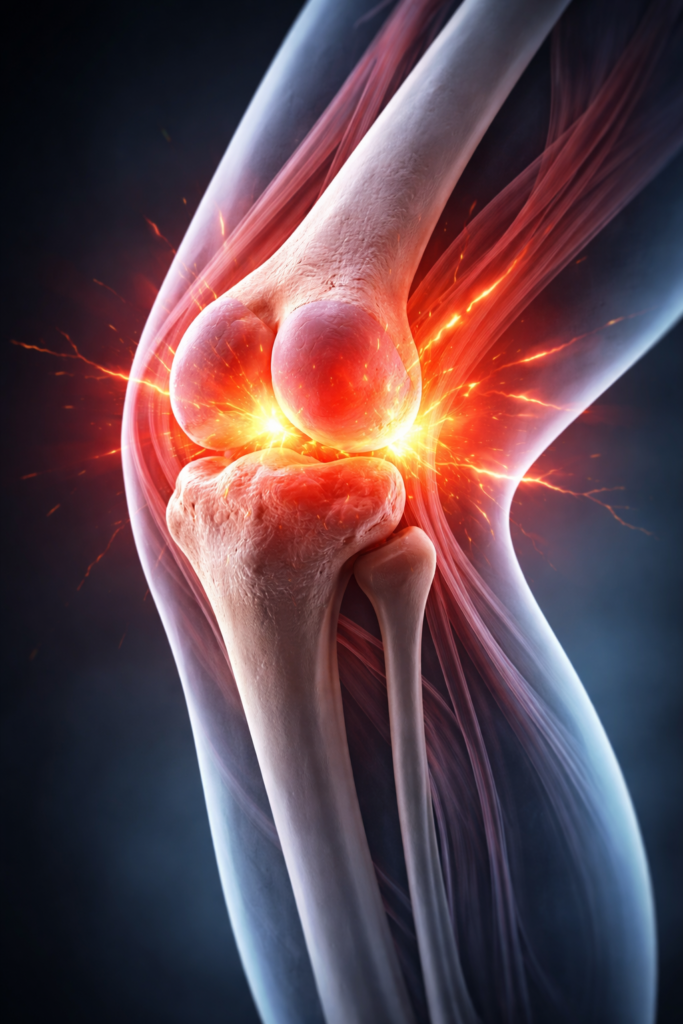

Natural Siddha Care for Knee Pain Relief

Siddha treatment for knee pain focuses on reducing inflammation, strengthening joints, and improving mobility. Using natural herbal medicines and traditional therapies, Siddha helps manage conditions like arthritis, joint wear, and age-related knee pain by treating the root cause.

Relieves knee pain and swelling naturally

Strengthens joints and improves flexibility

Supports long-term joint health without side effects